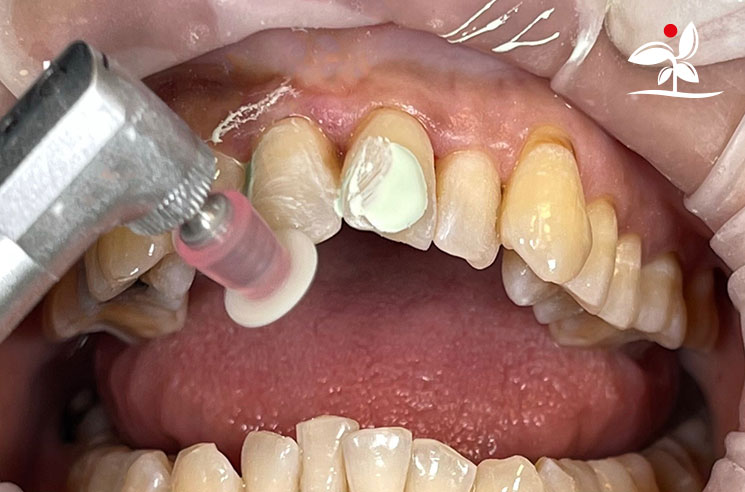

Restoration of Class IV Lesions using Naturomimetic Layering Technique (NLT) and Bioactive Restorative Materials

Dr Aung Pyae Phyo, Myanmar

With the growing awareness about the health, function and aesthetic benefits of preserving natural tooth structure, patients are now globally demanding for aesthetic dentistry with minimally invasive procedures that has a low biological cost. This public demand has encouraged logical clinicians to adopt to the minimally invasive cosmetic dentistry (MiCD) concept and its treatment protocol [1] in their practice. The author has been using MiCD concept and its treatment protocols since 2017, which

include the methods of treatment that are simple, fast, predictable and healthy. In aesthetic restoration, the tooth color restorative materials placement technique is one of the most challenging, confusing and frustrating areas to learn owing to the multiple techniques that have been proposed by many clinicians and replicating such techniques in practice is not always as easy as they are marketed in dentistry. Natural teeth are complex in structure and hard to simulate due distribution of colors through enamel and dentin [2]. Aesthetic restoration strategies should follow proper understanding of defects, right selection of restorative materials along with their proper application, finishing, texturing and polishing [2].